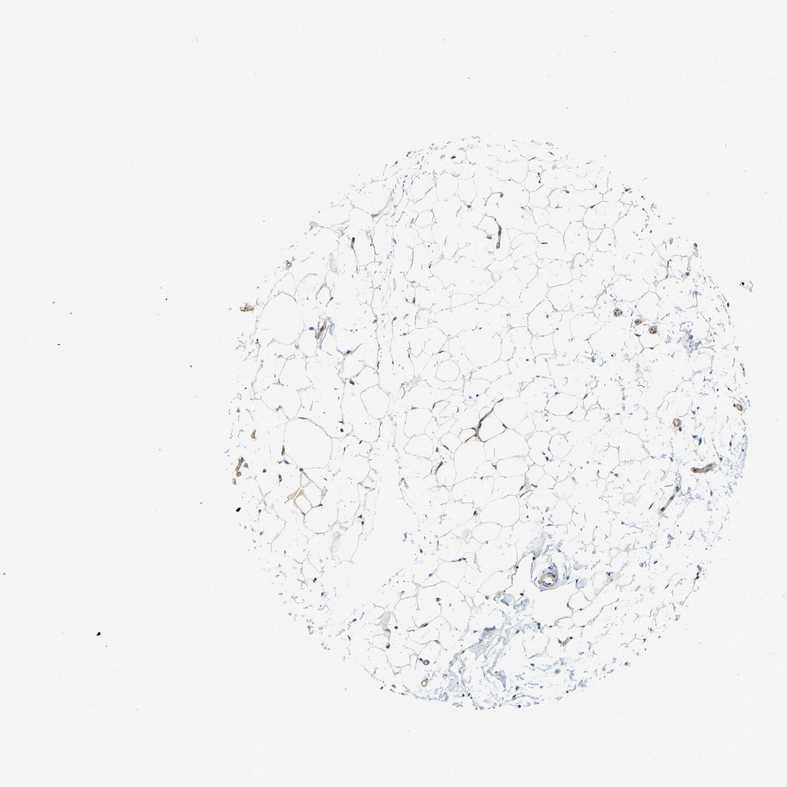

BREAST - Antibody stainingi

Antibody staining in the annotated cell types in the current human tissue is reported as not detected, low, medium, or high, based on conventional immunohistochemistry profiling in selected tissues. This score is based on the combination of the staining intensity and fraction of stained cells.

Each image is clickable and will lead to virtual microscopy that enables deeper exploration of all samples and also displays staining intensity scores, fraction scores and subcellular localization as well as patient and tissue information for each sample.

Antibody HPA018842Antibody HPA019076

Adipocytes Not detectedLow

Glandular cells Not detectedNot detected

Myoepithelial cells Not detectedNot detected